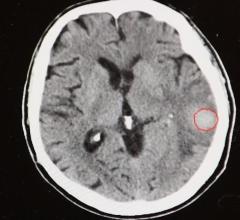

April 30, 2020 — An unprecedented collaboration among two medical societies and over 60 volunteer neuroradiologists has ...

April 9, 2020 — Care Mentor AI is developing an artificial intelligence (AI) system that will accelerate the analysis of ...